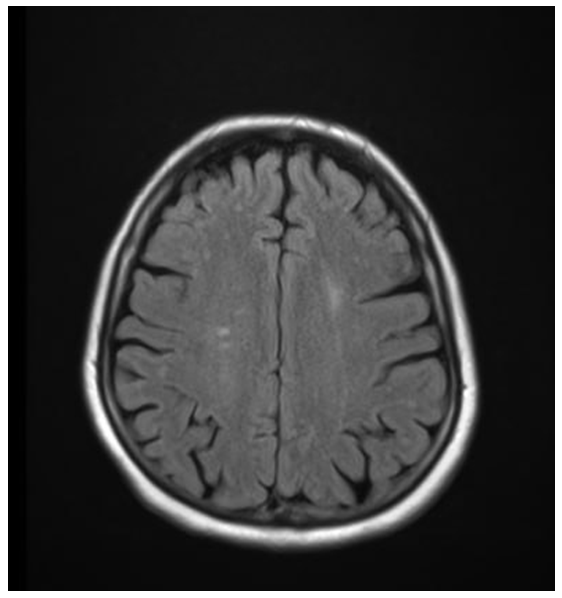

To objectively characterize brain damage in pregnant women with severe preeclampsia, magnetic resonance imaging (MRI) was performed using FSE_T2_FLAIR, T1_FLAIR, and DWI modes. The study was performed on axial, coronal, and sagittal sections with a 5-mm slice thickness.Brain MRIs (Figs. 1, 2) reveal areas of hyperintensity on FLAIR sequences, predominantly in the occipito-parietal regions of the white matter, with a tendency toward symmetrical distribution. These changes are characterized by vasogenic edema without signs of mass effect, midline displacement, hemorrhage, or ischemic injury. | Figure 1. MRI of the brain of patient Z.T., with severe preeclampsia (axial slice, FSE_T2_FLAIR mode): hyperintense foci of vasogenic edema in the occipital-parietal regions |

| Figure 2. MRI of the brain of the same patient: symmetrical areas of increased signal on FLAIR, characteristic of posterior reversible encephalopathy syndrome (PRES) |

The ventricular system is not dilated, the contours are clear, and the subarachnoid spaces are not deformed. On FSE_T2 and T1 FLAIR sections, the structure of the corpus callosum and brainstem is preserved, and no signs of focal necrotic changes are detected. Dynamic observation 10-14 days after delivery showed regression of foci of hyperintensity, confirming the reversible nature of the process.The obtained data indicate the presence of typical MRI signs of reversible posterior encephalopathy syndrome (Posterior Reversible Encephalopathy Preeclampsia Retinopathy Syndrome (PRES) occurs in patients with severe preeclampsia. This syndrome develops as a result of hypertensive crisis, endothelial dysfunction, and impaired cerebral blood flow autoregulation, leading to increased permeability of the blood-brain barrier and the development of vasogenic edema.Visualized areas of hyperintensity in the white matter of the parieto-occipital lobes reflect reversible perfusion disturbances. The absence of signs of cytotoxic edema and necrosis confirms the benign nature of the process, provided blood pressure is corrected promptly and delivery is performed.Correlation analysis showed a significant relationship between the severity of hyperintensive changes and hemodynamic parameters (r = 0.62; p < 0.01) and coagulation status (r = 0.58; p < 0.05), which reflects the systemic nature of vascular disorders in severe preeclampsia.Table 1 presents the data of the general blood test in pregnant women with severe (group 1a) and moderate (group 1b) preeclampsia compared to the control group.Table 1. Main indicators of general blood analysis in examined pregnant women (M ± m)  |

Summarizing all the data in our study, we can conclude that in pregnant women with severe preeclampsia, brain MRI reveals symmetrical hyperintense foci in the occipito-parietal regions, consistent with vasogenic edema. These changes are characteristic of posterior reversible encephalopathy syndrome (PRES), confirming the presence of systemic endothelial dysfunction and hypertensive CNS damage. Following stabilization of blood pressure and delivery, MR changes reverse, demonstrating the reversibility of cerebral dysfunction. Thus, the biochemical profile in pregnant women with preeclampsia of varying severity is characterized by increasing signs of multiple organ dysfunction as the disease worsens, consistent with clinical manifestations and MRI findings confirming the development of reversible encephalopathy.